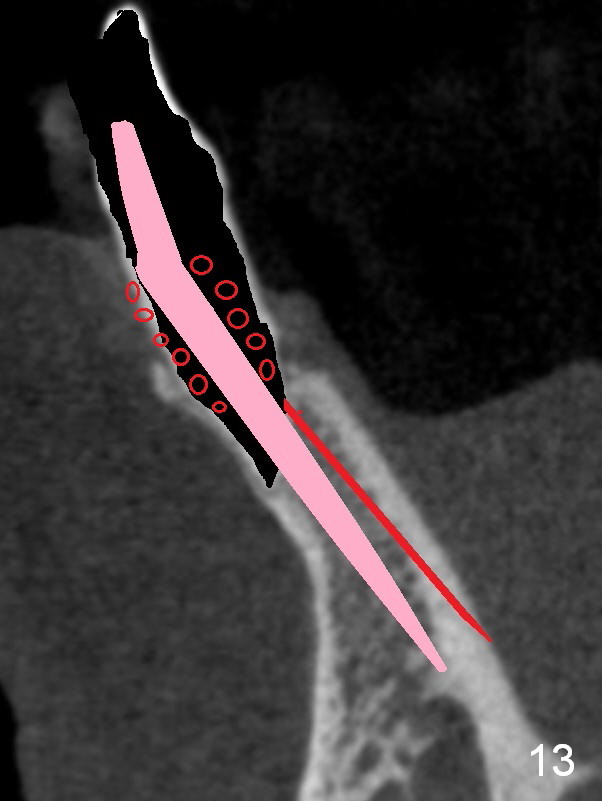

A 74-year-old man has several missing teeth (Fig.1). His 1st goal is to replace the lower left lateral incisor (Fig.2). The residual root has an apical lesion (Fig.3 *). To describe intraop findings, a CT image of a different patient is used (Fig.4 coronal section; B: buccal; L: lingual). After extraction, the buccal plate is found to be thin and low (Fig.5 arrowheads). A 1.5 mm pilot drill (Fig.6 red line) is used to initiate osteotomy in the lingual plate of the socket. Once the drill penetrates the lingual plate, the trajectory changes and the depth is 17 mm from the gingival margin (Fig.7). A PA is taken (Fig.8); it appears that the osteotomy can be extended more apically. When the pilot drill extends to 20 mm, there is sudden empty feeling. The lingual plate has perforated (Fig.9). A new osteotomy is established buccally (Fig.10 pink). To avoid buccal plate perforation, especially in the buccal undercut area (>), the coronal end of the drill has to be tilted buccally (<--). An angled abutment (3x20 mm, 15°) is placed (Fig.11,12). The abutment is modified (Fig.13,14) to accommodate an immediate provisional (Fig.15,16 P). Perio dressing is to be applied to prevent the bone graft from getting dislodged buccally (Fig.15). The dressing is in place 7 days postop (Fig.17).